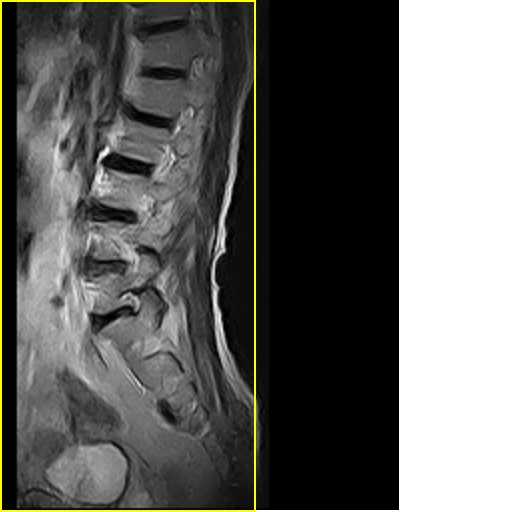

标题: MRI0859:[原创]腰椎,男,78岁,右下肢跛行两月 [打印本页]

男,78岁,右下肢跛行两月.

右侧黄韧带肥厚或钙化,压迫马尾神经所致。必要时行ct扫描。

腰间盘膨出、黄韧带肥厚、可疑先天性腰椎管狭窄。

退行性骨关节病:增生、椎间盘变性、膨出...

退行性病变:增生、椎间盘变性、膨出[l4-5、l5-s1 椎间盘膨出]

退行性骨关节病:增生、椎间盘变性、膨出..黄韧带肥厚.

黄韧带肥厚.